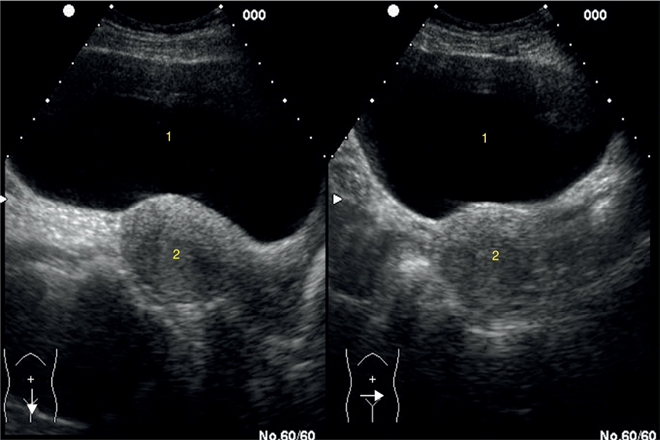

La ecografía vésicoprostática con evaluación del residuo postmiccional y la uroflujometría son también estudios diagnósticos opcionales, que pueden colaborar en el seguimiento y en la toma de decisiones terapéuticas.